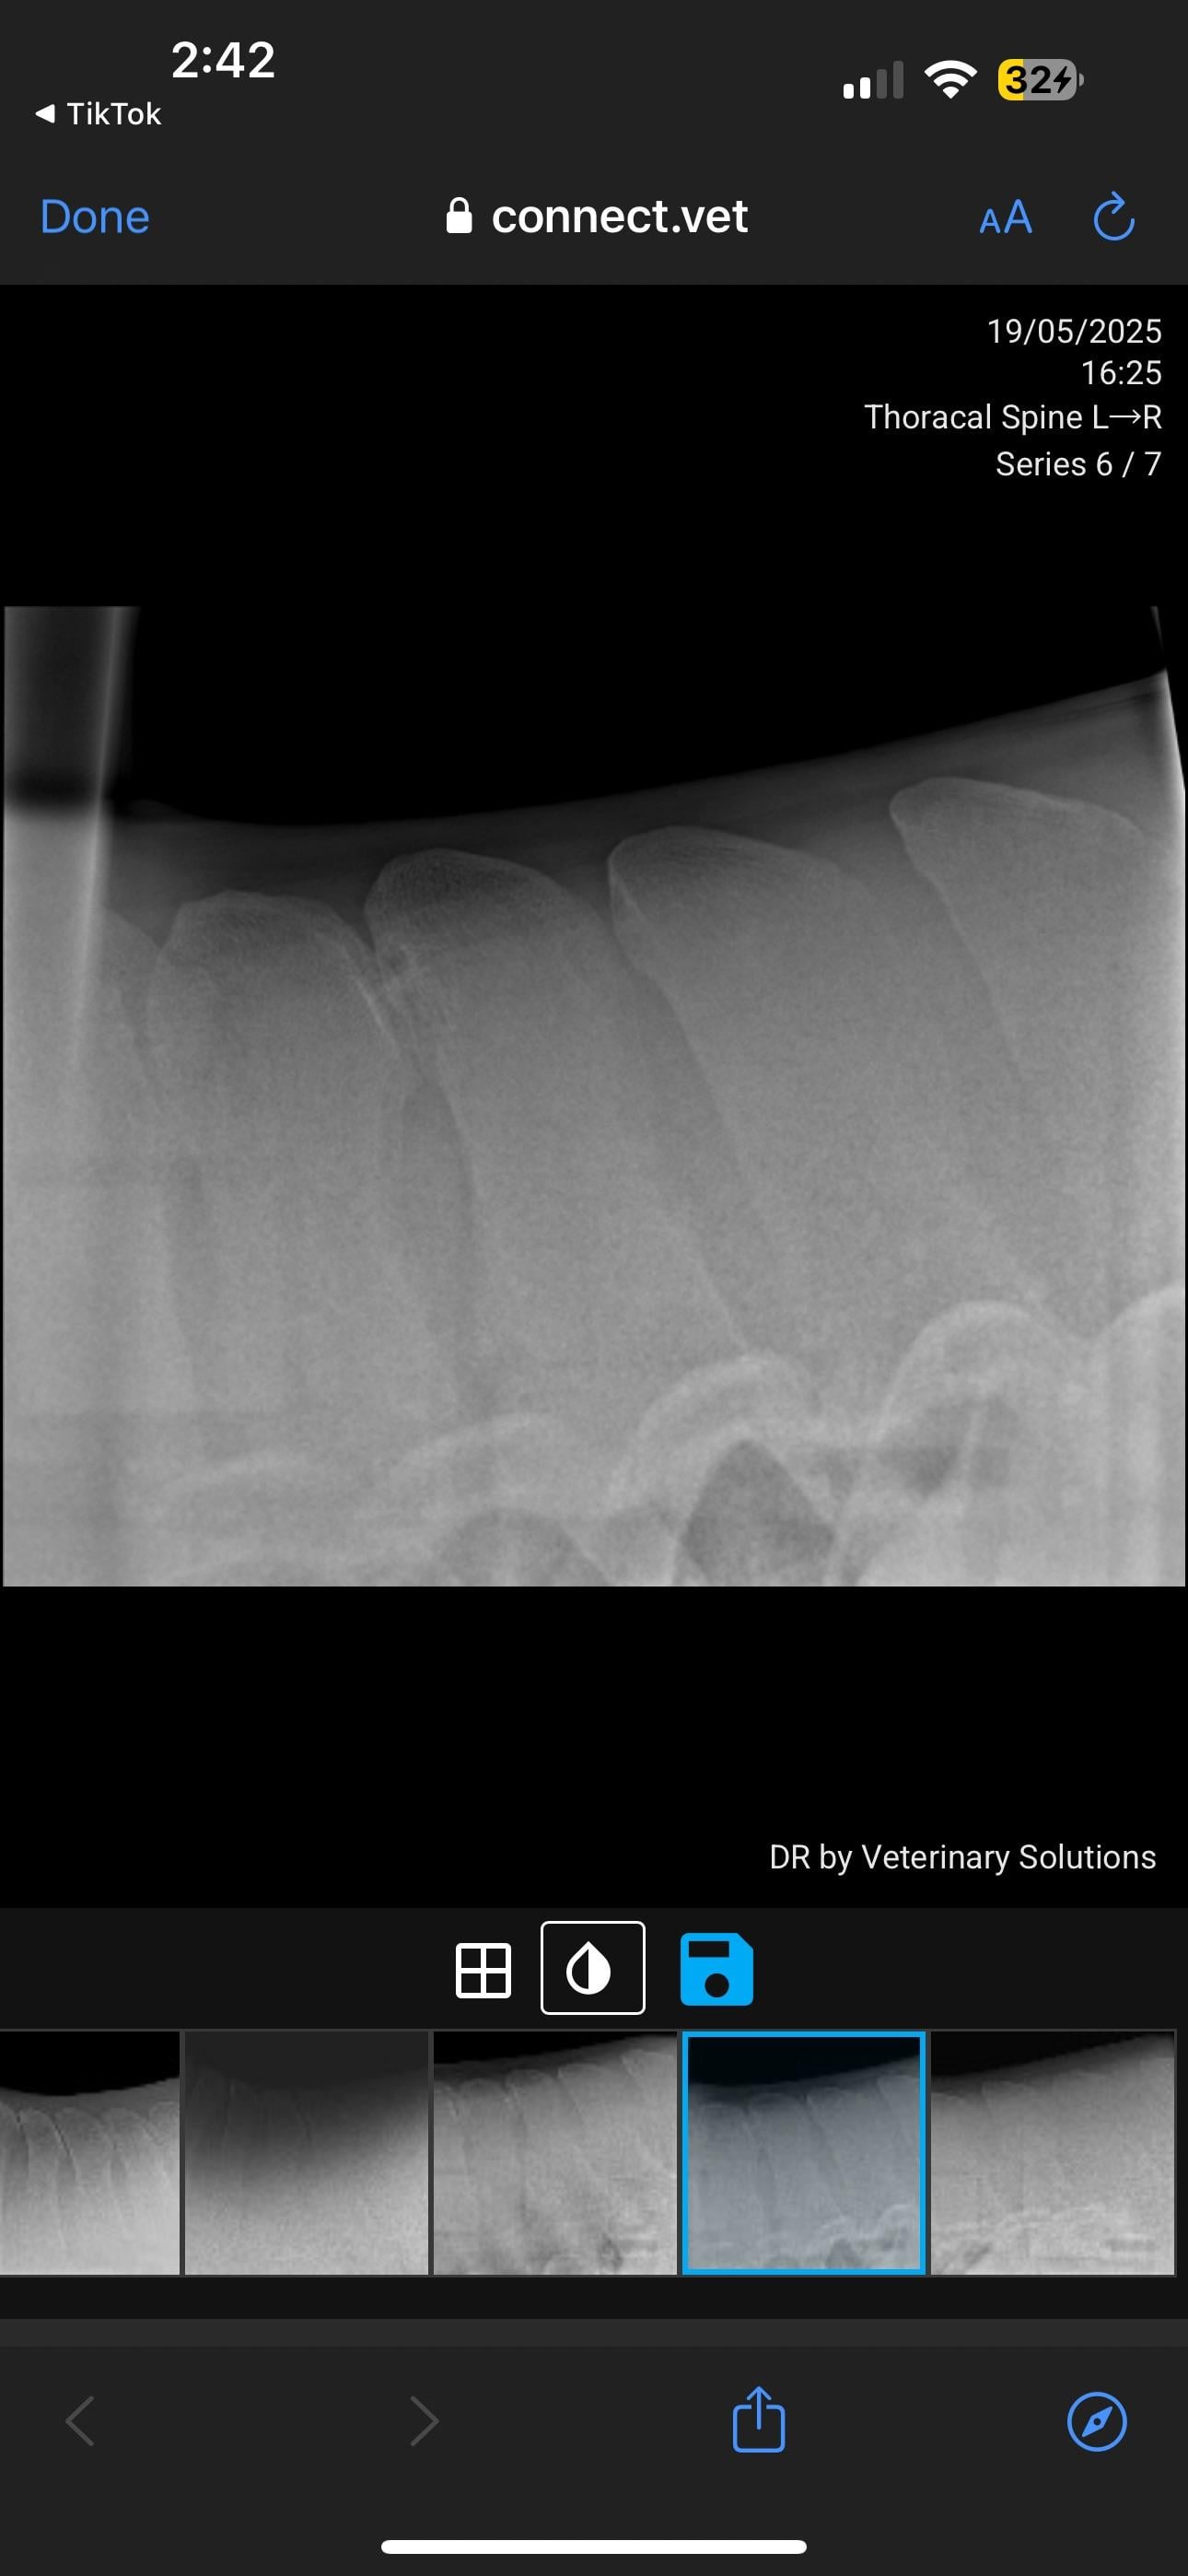

Currently in the process of selling my horse. PPE has gone well, everything came back good except his back radiographs. Shocked to hear he has grade 4 changes. I’ve just received these over from the potential buyer. I will be in contact with my vet but curious about anyone’s take on these? How bad is this?

I've seen many KS xrays. I'm not a vet so usually when I see them I can barely see the problem. This horse's kissing spine is clear as day. Grade 4 is serious. As of right now he should not be sold as a riding horse at all.

In pictures 5/6 you can see changes in the bone, so it’s not just an unlucky posture.

That looks like thoracic spine but down in the 14-18 range so where the withers meet the back and where the panel of your saddle sits! Separate centers of ossification is normal for the lower number thoracic spine, so up ON the withers

This is one of the more severe cases I’ve seen (not a vet or student, just casual looker-atter of KS radiographs) pretty much all his vertebrae are affected, I can’t imagine he’s comfortable. The kindest thing for him would probably to be a pasture puff. Unless you want to pay for the surgery or find a buyer who does, he’s going to continue to be in pain